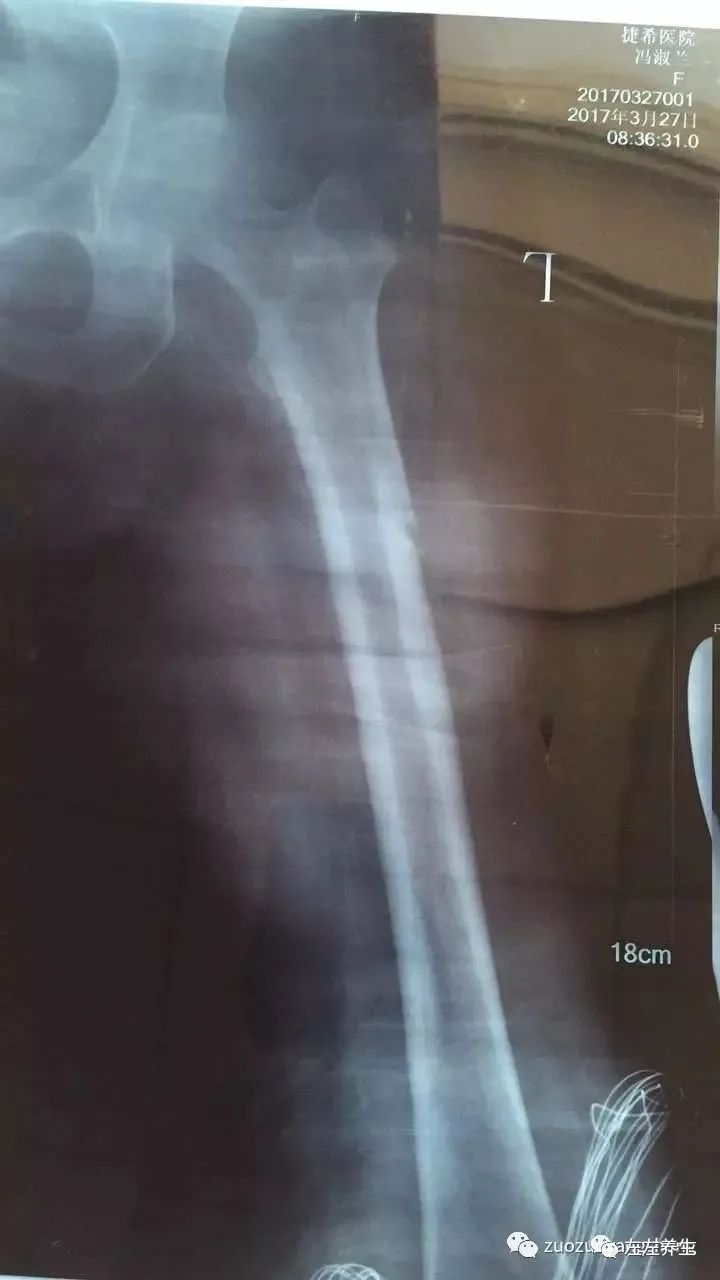

① 刚骨折时(点击可看大图)

② 刚骨折时(点击可看大图)

牵引期间,在骨折处时敷药酒时敷姜膏、贴暖宝宝、喝姜汤,后改为喝参粉汤(1天4次)。医生说牵引需要8到12周,但我母亲在牵引4周时就已长出一些骨架,考虑到年龄因素继续牵引至6周,拍片显示骨头愈合非常良好,开始慢慢撤牵引,医生建议再继续在医院多观察两周,然后就可以回家安养。在这治疗过程当中,运用原始点的方法帮着内外调理,取得了显著的效果,被医生称之为奇迹,并成为医院的案例,可以作为以后同样患者治疗的一个指导。